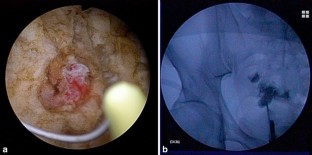

While there have been numerous reports about colovesical fistulas and ruptured intestinal diverticula, there have been far fewer reports about vesicointestinal fistulas caused by Meckel’s diverticula. Most Meckel’s diverticula are asymptomatic. Furthermore, they seldom cause vesicointestinal fistulas, and the associated complications are non-specific. Thus, their preoperative diagnosis is difficult. We experienced a case in which a vesicointestinal fistula was caused by a Meckel’s diverticulum and was treated with laparoscopic surgery. A 46-year-old male was referred to our hospital after exhibiting hematuria. Cystoscopy revealed a fistula between the small intestine and bladder. Contrast-enhanced computed tomography and magnetic resonance imaging showed a diverticulum in the ileum and a fistula between the ileum and bladder, which passed through the diverticulum. A Meckel’s diverticulum was suspected. We conducted a laparoscopic operation. We dissected the Meckel’s diverticulum with an automatic suturing device and removed it together with part of the ileum. The patient’s postoperative course was good. We experienced a case in which a vesicointestinal fistula was caused by a Meckel’s diverticulum and was successfully treated with laparoscopic surgery. In selected cases of Meckel’s diverticulum, the dissection of the diverticulum with an automatic suturing device is appropriate.

Fig. 1